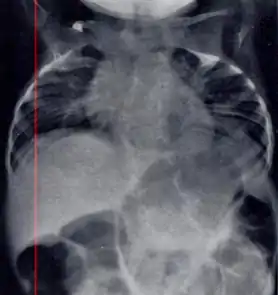

| Radiograph depicting typical skeletal features of Jarcho-Levin syndrome, subtype spondylothoracic dysplasia. Note fanlike configuration of the ribs, with extensive posterior fusion, along with multiple vertebral segmentation defects. | |

Spondylothoracic dysplasia

Spondylothoracic dysplasia, or STD, has been repeatedly described as an autosomal recessively inherited condition that results in a characteristic fan-like configuration of the ribs with minimal intrinsic rib anomalies. Infants born with this condition typically died early in life due to recurrent respiratory infections and pneumonia due to their restricted thorax.[3][4][5] Recently, a report[6] has documented that actual mortality associated with STD is only about 50%, with many survivors leading healthy, independent lives.

Spondylocostal dysostosis

In contrast to STD, the subtype spondylocostal dysostosis, or SCD features intrinsic rib anomalies, in addition to vertebral anomalies. Intrinsic rib anomalies include defects such as bifurcation, broadening and fusion that are not directly related to the vertebral anomalies (such as in STD, where extensive posterior rib fusion occurs due to segmentation defects and extreme shortening of the thoracic vertebral column).[6] In both subtypes, the pulmonary restriction may result in pulmonary hypertension, and have other potential cardiac implications.[7]